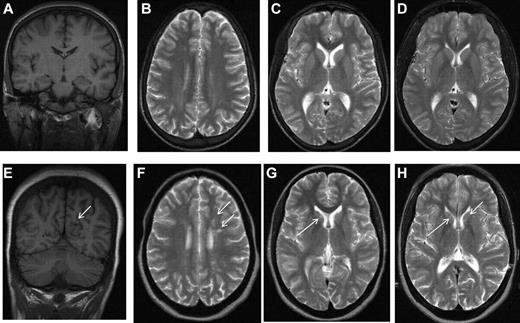

The largest longitudinal cohort study to address the prevalence and incidence of SCI in children with SCA was the CSSCD, an observational study of children identified as infants and followed closely over the subsequent decade, which used MRI of the brain to detect abnormally increased T2-weighted signal intensity on multiple views (Figures 1 and 2) in children without current focal neurologic deficits as assessed by a hematologist. Previous neurologic history other than seizures, for example, coma, dizziness, ataxia, or transient focal weakness, was not explored. Hematologists may have discounted subtle neurologic findings that may have classified as abnormal and suggesting a prior overt stroke if reviewed by neurologists.6 The more precise definition used by Casella et al7 in The Silent Cerebral Infarct Trial (SIT Trial)7,8 included a MRI lesion measuring at least 3 mm in greatest linear dimension, visible in at least 2 planes of T2-weighted images (axial and coronal; Figure 2B-C). The SIT Trial definition excluded prior seizures and required no current focal neurologic deficit that could be explained by the anatomic location of the presumed SCI. Thus, individuals could have a focal neurologic examination, for example, compatible with a peripheral neuropathy, but would still meet the definition of SCI if the location of the infarct would not account for the neurologic deficit.

MRI in sickle cell disease. Coronal T1-weighted MRI (A,E) and axial T2-weighted MRI (B-D,F-H) in patients with homozygous SCA. (A-C) Normal MRI in a 19-year-old man with homozygous SCA. (D) Three years later, there is no change. (E-G) Silent infarction (arrows) in the frontal white matter and basal ganglia in a 15-year-old girl with cognitive problems affecting school performance but no acute neurologic presentation. (H) Three years later she has further infarcts with evidence of mild generalized atrophy and had a transient right hemiparesis as well as developing signs of a diplegia.

In the first systematic study of SCI in adults with SCA, Vichinsky et al used a definition of a minimum of 5 mm signal hyperintensity in the T2-weighted image,9 but to be included, lesions also had to show corresponding hypointensity on the T1-weighted image (Figures 1E, 2A). Normal adults typically accumulate T2 hyperintensities as they age, but children do not. This more restrictive definition of SCI and the distinction from encephalomalacia and atrophy (Figures 1H, 2D-H) parallels the descriptions used in general populations of asymptomatic elderly adults with SCI.10

As part of the protocol for the observational CSSCD cohort, the leadership group added serial surveillance MRI scans of the brain of children beginning at 6 years of age. A total of 266 children with SCA hemoglobin SS (HbSS) completed both a MRI of the brain and a battery of age-appropriate tests of cognitive function. The average age at initial scan was 8.3 years with each child having at least 1 follow-up scan at a mean of 12.1 years of age. The mean interval between first and follow-up studies was ∼ 2 years. In this cohort, the prevalence of SCI at baseline was 21.2%.15 SCIs commonly differ in size and location compared with overt strokes. Whereas overt strokes are typically located in both cortex and deep white matter,16 SCI in the CSSCD typically occurred in the deep white matter of the frontal (81%; Figure 1E-F) or parietal (45%) lobes (Figure 2A-D), followed in frequency by the basal ganglia (Figure 1G-H) or thalamus (16%) and the temporal lobes (9%).15 Similar observations were reported for an unselected cohort of 132 children with SCA in Créteil, France undergoing brain MRI as part of routine medical care2 and in other studies.4,5,17,18 SCI in SCA are typically smaller in size compared with overt strokes. In the CSSCD participants, 83% of the children with overt strokes, but only 16% of those with SCI, had lesions that were at least 1.5 cm.15